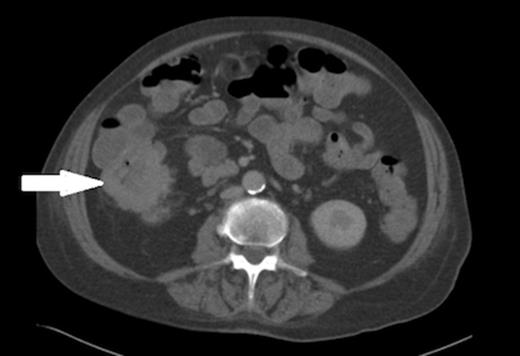

Urine microscopy was normal but blood cultures taken on the day of admission grew Escherichia coli (E. coli) and this, coupled with iron deficiency anaemia prompted a search for other pathology and a CT scan of chest, abdomen and pelvis showed thickening of the ascending colon (figures 2 and 3). A colonoscopy confirmed a fungating lesion in the mid-ascending colon and biopsies showed adenocarcinoma of the colon. Our patient then had a laparoscopic right hemicolectomy followed by adjuvant chemotherapy for a moderately differentiated adenocarcinoma (pT4 N2 V1 R0 M0). Her discitis settled with antibiotic treatment.

Coronal view of the CT abdomen showing thickening of the ascending colon (indicated by arrow).